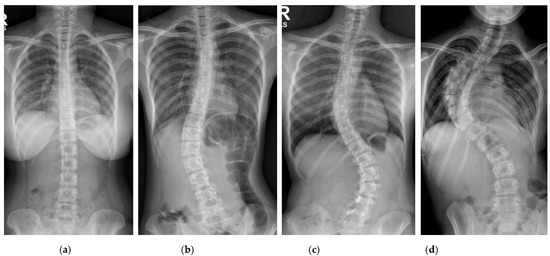

The Cobb angle measurement of the scoliotic spine is prone to inter- and intra-observer variations in the clinical setting. This paper proposes a deep learning architecture for detecting spine vertebrae from X-ray images to evaluate the Cobb angle automatically. The public AASCE MICCAI 2019 anterior-posterior X-ray image dataset and local images were used to train and test the proposed convolutional neural network architecture. Sixty-eight landmark features of the spine were detected from the input image to obtain seventeen vertebrae on the spine. The vertebrae locations obtained were processed to automatically measure the Cobb angle. The proposed method can measure the Cobb angle with accuracies up to 93.6% and has excellent reliability compared to clinicians’ measurement (intraclass correlation coefficient > 0.95). The proposed deep learning architecture may be used as a tool to augment Cobb angle measurement in X-ray images of patients with adolescent idiopathic scoliosis in a real-world clinical setting. Full article

Figure 1